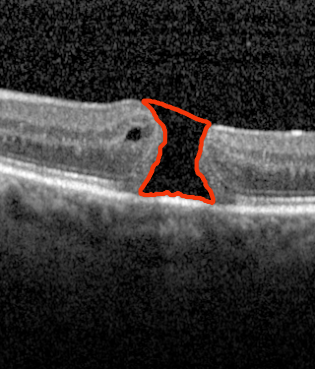

Figure 2: Qualitative sample output of our trained macular hole model (M1subscript𝑀1M_{1}) compared with the ground truth, the state-of-the-art automated approach (Nasrulloh) [9], the residual model (M2subscript𝑀2M_{2}) and DeepMind’s model (M3subscript𝑀3M_{3}). For clarity, we zoomed in on the predicted regions.

The qualitative results of running the trained macular hole models are generally quite close to the ground truth, as seen in Figure 2. In general, predictions from the models are closer to the ground truth than the state-of-the-art automated approach. 3D visualizations of the output of our proposed model can be seen in TABLE I.